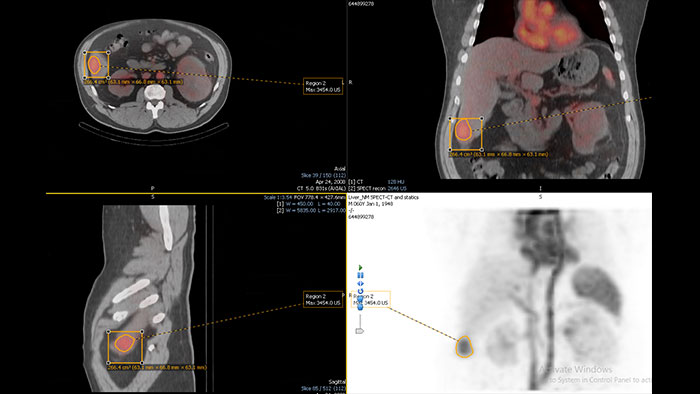

Evaluate fused coronary anatomy

Emory Cardiac Toolbox (ECTb) HeartFusion offers fusion of a patient’s coronary tree from cardiac CT angiography with MI perfusion images.

Benefits

*Emory Cardiac Toolbox, ECTb, HeartFusion, and SyncTool are registered trademarks of Emory University.